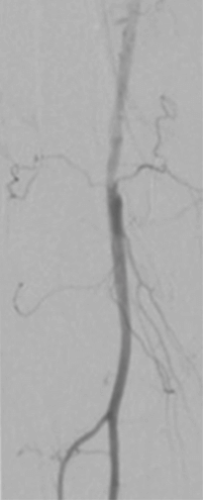

Results

The final angiography showed complete revascularization of the femoropopliteal segment (Figure 2).